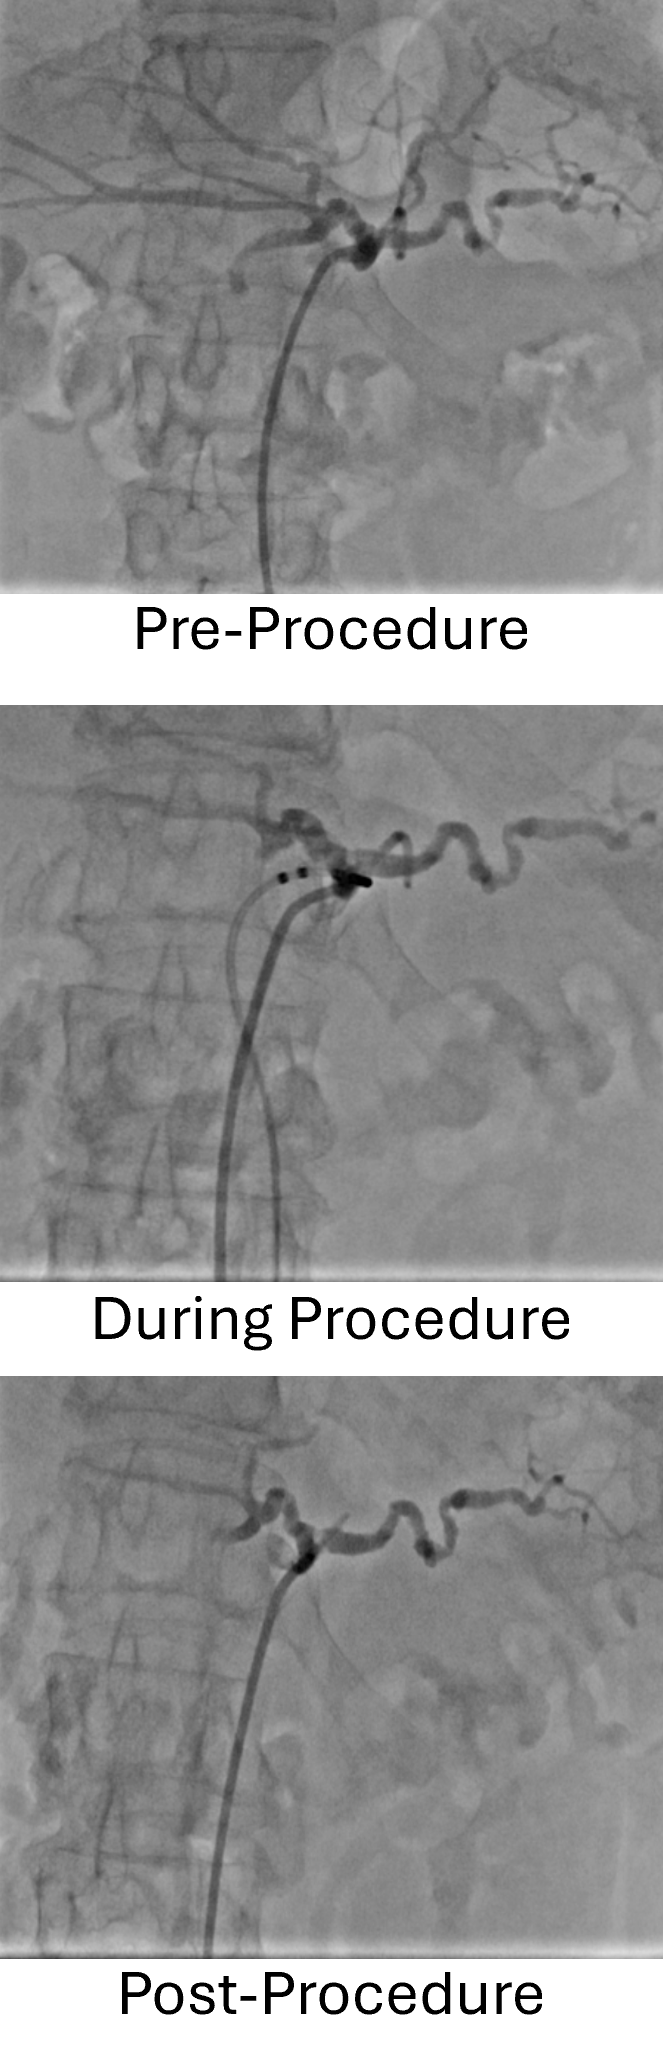

“Our abstract reports findings from a first-in-human proof-of-concept study evaluating transvascular RF denervation of the celiac plexus in patients with refractory pancreatic cancer–related abdominal pain,” said researchers from AKFA Medline Hospital in Uzbekistan, the University of British Columbia, and Autonomix Medical, Inc. “The goal was to assess procedural feasibility, safety and early clinical outcomes.”

In this prospective study, 19 of 20 enrolled patients underwent successful treatment, corresponding to a 95% procedural feasibility rate, researchers said. This total population group observed significant reductions in pain as early as 24 hours following the procedure, with mean pain reductions exceeding 40% through three months of follow-up. Importantly, there were no device- or procedure-related serious adverse events.

“100% of subjects who underwent a femoral access procedure responded to treatment,” researchers said. That group had a 59% reduction in pain, and 100% of responding patients were opioid-free within 7 days. At 4-6 weeks, 73% remained opioid free.

“We also learned that patients with brachial access did not respond, marking an important procedural finding,” they said. “These results provide early clinical evidence that transvascular neuromodulation can be performed safely and may meaningfully reduce severe pancreatic cancer–related pain."